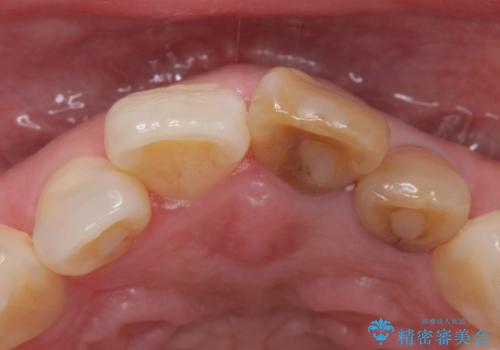

- 前歯の変色を主訴に来院された患者様です。

再根管治療からのやり直しも提案しましたが、特にご希望されなかったためクラウンでの修復処置のみ行います。

歯は根管治療が終了して時間が経つとだんだん茶色く変色していきます。